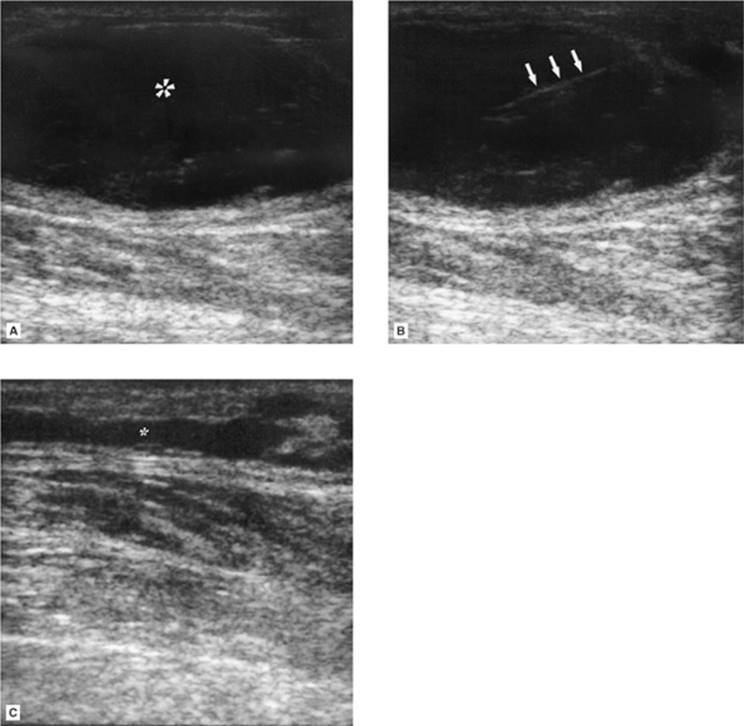

Figure 35.2. A 74-year-old patient on Coumadin developed a focal lower extremity area of swelling, erythema, and progressive pain adjacent to the knee following trauma. A: Ultrasound (US) examination demonstrates a 5.5-mL hypoechoic superficial fluid collection (asterisk). B: Hyperechoic needle (arrows) seen entering the fluid collection. C: Postevacuation US demonstration near complete drainage of the fluid collection (asterisk). The fluid was sterile and consistent with liquefied hematoma.